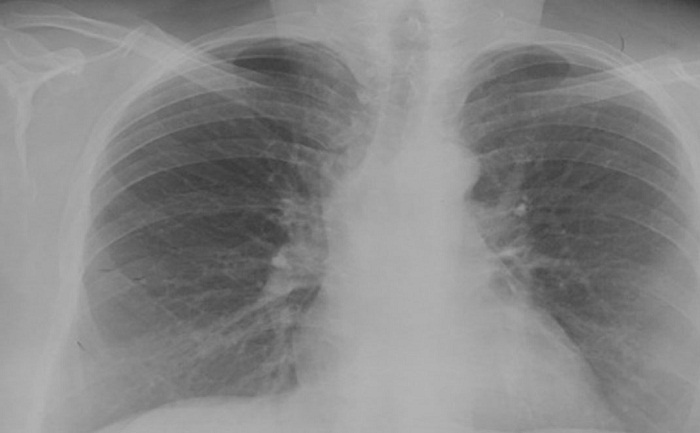

El síndrome de Gorlin-Goltz, también llamado síndrome del nevoide de células basales, se caracteriza por presentar anomalías del desarrollo que se manifiestan clínicamente con la presencia de numerosos CBC micro- y macroscópicos, hamartomas benignos del folículo piloso, queratoquistes odontogénicos mandibulares, hiperqueratosis palmoplantar, anomalías esqueléticas (costillas bífidas, sindactilia), características craneofaciales específicas (cráneo agrandado, hipertelorismo y prominencia frontal), calcificaciones intracraneales ectópicas y dismorfia facial con macrocefalia, fisura labiopalatina y anomalías oculares graves (1,4). En 2007, Moctezuma y colaboradores (19) indicaron los criterios para el diagnóstico del síndrome de Gorlin. Según estos autores, se requiere que el paciente cumpla con dos criterios mayores y un criterio menor o un criterio mayor y dos criterios menores (20,21). El diagnóstico de síndrome nevoide de células basales de la paciente de este artículo se confirmó con exámenes complementarios: radiografías de tórax y simple de cráneo (figuras 9 y 10).

* Partes blandas normales, estructuras óseas conservadas, corazón de tamaño normal, cayado aórtico de calibre normal, ausencia de adenopatías.

* Suturas craneales normales, surcos vasculares normales, arcos cigomáticos y silla turca normal, calcificaciones fisiológicas de la hoz cerebral.

Después del seguimiento multidisciplinario que se dio a la paciente, se pudo identificar la presencia de criterios mayores (presencia de dos o más CBC, piqueteado palmoplantar) y menores (calcificación laminar de la hoz del cerebro, antecedente de fibromas ováricos) que permitieron establecer el diagnóstico de síndrome de Gorlin-Goltz o síndrome nevoide de células basales y remitir a la paciente a las especialidades médicas en la institución de salud pertinente (Instituto Nacional de Cancerología) para poderle brindar un tratamiento integral.